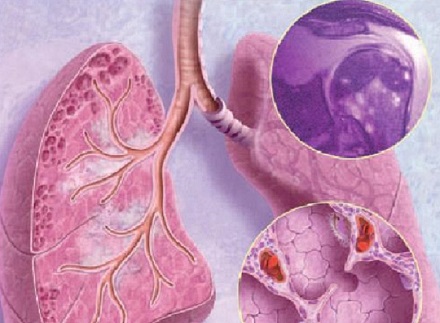

Саркоидоз легких (гранулематоз доброкачественного характера) — это заболевание, поражающее разные ткани организма. Но чаще все он проявляется в органах дыхания. При этой болезни в легких, а также в трахее, бронхах и лимфоузлах образуются гранулемы.

Опасность саркоидоза в том, что гранулемы постепенно растут, сливаются, затем рассасываются и оставляют после себя рубцовую ткань. Это сильно влияет на работу органов — в частности, легких — которые не могут полностью выполнять свои функции. При поверхностной вентиляции функция дыхания нарушается — а это, как известно, влечет за собой нагрузку на все внутренние органы, потому что кровь не может снабдить кислородом разные системы организма.

Выделяют три стадии саркоидоза. На первой наблюдается увеличение лимфатических узлов, поражение легких либо одностороннее, либо симметричное. Вторая стадия характеризуется распространением болезни по лимфатическим путям. Гранулемы еще маленькие, легочная ткань постепенно начинает заменяться тканью более высокой плотности.

На третьей стадии соединительная ткань разрастается в альвеолах, образуются рубцы. Высоки риски таких осложнений, как эмфизема, пневмосклероз. Часто гранулемы растут одновременно и в легких, и в других частях организма.